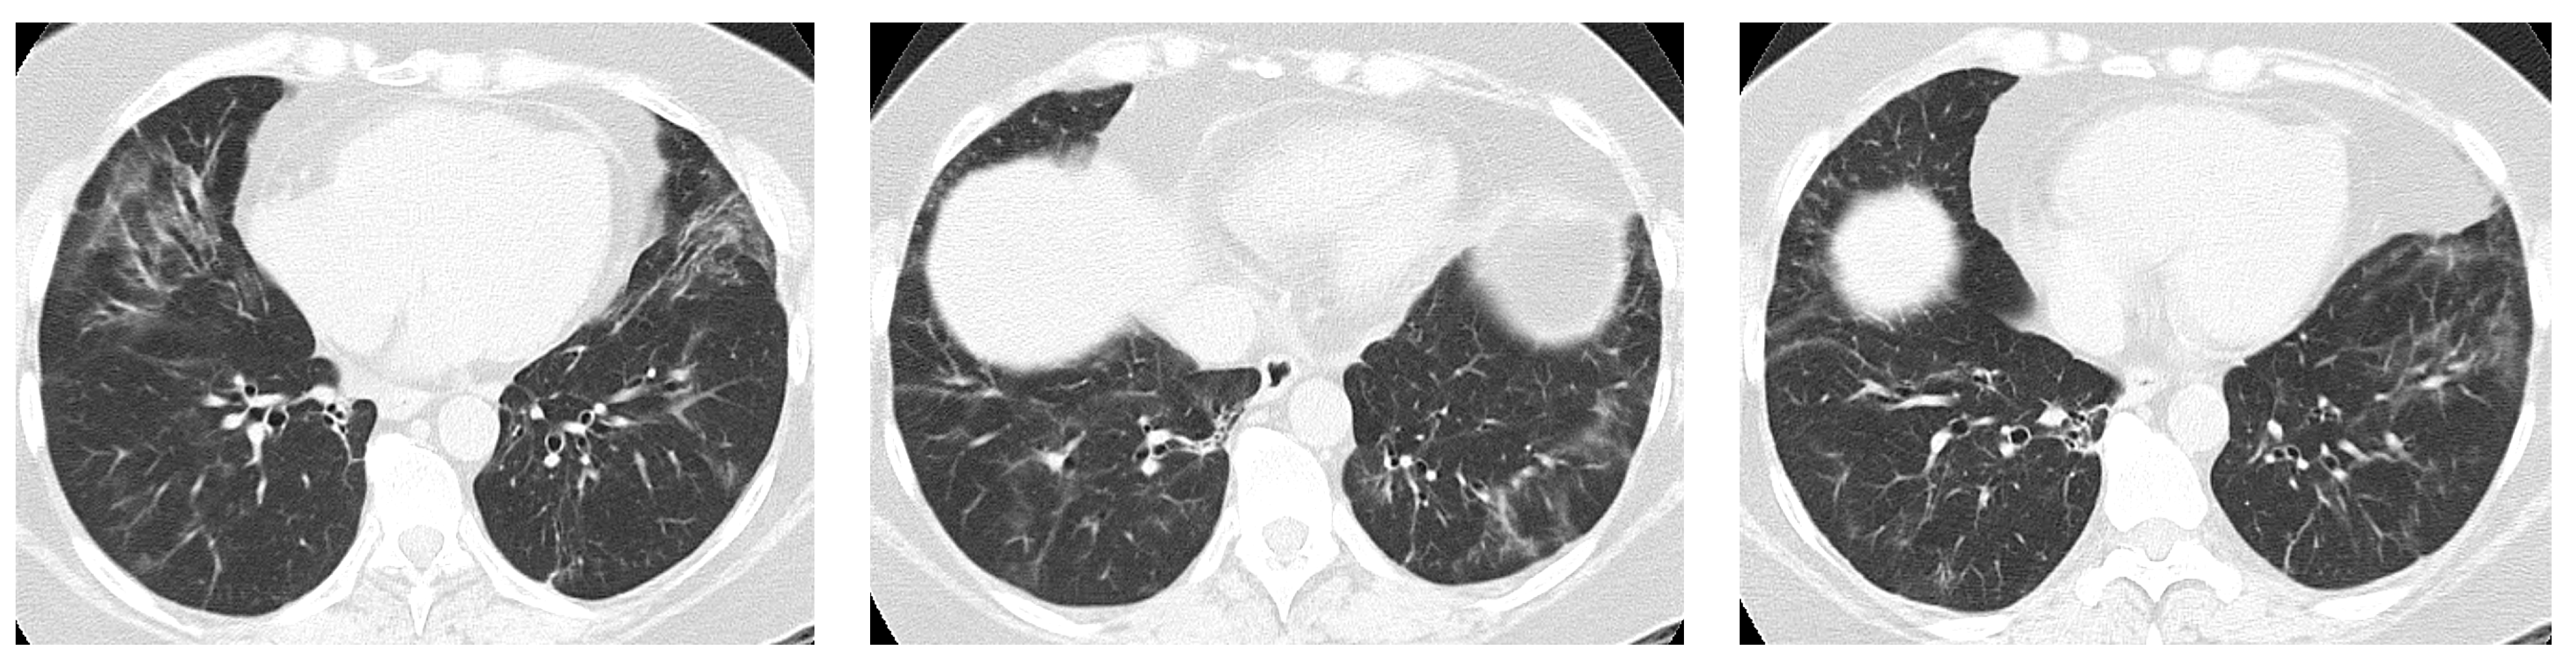

4. Imaging and Histopathology of ILD in pSS

4.1. How Does Radiologic/Histopathologic Pattern Influence the Clinical Picture and Management of pSS-ILD Patients? What Is the Role of Lung Biopsy?

- Egashira, R.; Kondo, T.; Hirai, T.; Kamochi, N.; Yakushiji, M.; Yamasaki, F.; Irie, H. CT Findings of Thoracic Manifestations of Primary Sjögren Syndrome: Radiologic-Pathologic Correlation. Radiographics 2013, 33, 1933–1949. [Google Scholar] [CrossRef] [PubMed]

- Flament, T.; Bigot, A.; Chaigne, B.; Henique, H.; Diot, E.; Marchand-Adam, S. Pulmonary manifestations of Sjögren’s syndrome. Eur. Respir. Rev. 2016, 25, 110–123. [Google Scholar] [CrossRef]

- Dong, X.; Zhou, J.; Guo, X.; Li, Y.; Xu, Y.; Fu, Q.; Lu, Y.; Zheng, Y. A retrospective analysis of distinguishing features of chest HRCT and clinical manifestation in primary Sjögren’s syndrome-related interstitial lung disease in a Chinese population. Clin. Rheumatol. 2018, 37, 2981–2988. [Google Scholar] [CrossRef]

- Dong, X.; Gao, Y.-L.; Lu, Y.; Zheng, Y. Characteristics of primary Sjögren’s syndrome related lymphocytic interstitial pneumonia. Clin. Rheumatol. 2021, 40, 601–612. [Google Scholar] [CrossRef] [PubMed]

- Ito, I.; Nagai, S.; Kitaichi, M.; Nicholson, A.G.; Johkoh, T.; Noma, S.; Kim, D.S.; Handa, T.; Izumi, T.; Mishima, M. Pulmonary manifestations of primary Sjogren’s syndrome: A clinical, radiologic, and pathologic study. Am. J. Respir. Crit. Care Med. 2005, 171, 632–638. [Google Scholar] [CrossRef]